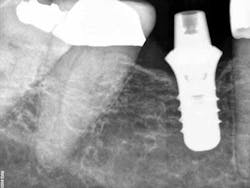

Fig. 1: X-ray of torqued-in prefabricated abutment. The final impression was taken, and a temporary was placed at this visit.